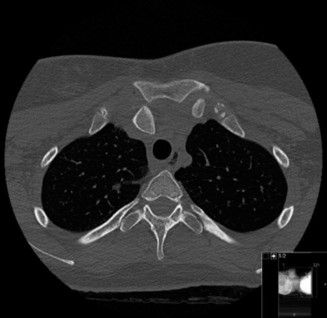

The correct answer is (B). An MRI showing a rotator cuff tear is considered diagnostic of a rotator cuff tear because of its high sensitivity, specificity, and accuracy. It has superb soft tissue imaging abilities (see Fig. 2–5). However, it should be noted that while MRI usually can differentiate between partial- and full-thickness rotator cuff tears, this varies with the power and accuracy of the MRI facility. This is also true with the ability of MRI to differentiate between partial-thickness rotator cuff tears and subacromial bursitis. An arthroscopy is needed for definitive differentiation of these pathologies.

Figure 2–5_Coronal oblique view MRI slice of a left shoulder. (Reproduced with permission from Smithius R and van de Woude HJ. Shoulder MR Anatomy: Normal Anatomy, Variants, and Checklist. _Radiology Assistant. April 2, 2012.)

Shoulder CT scans (Answer A) are not typically used to diagnose rotator cuff tears. X-rays, aka roentgenograms (Answer C), can show signs of rotator cuff pathology but are not diagnostic. Some signs of chronic rotator cuff tears that are sometimes seen on AP view x-rays include calcific tendonitis, calcification of the coracohumeral ligament, proximal migration of the humerus, and cystic changes of the greater tuberosity. An outlet view x-ray can show a type III (hooked) acromion, which is correlated with a higher rate of rotator cuff tears, or an OS acromiale, which would require special consideration for surgical treatment. Shoulder arthrograms (Answer D) are used primarily only when MRI is contraindicated and are considered positive for a rotator cuff tear if dye leaks from the glenohumeral joint into the subacromial space. MR arthrogram (Answer E) has been shown to have equivalent diagnostic ability compared with standard MRI and can be used to diagnose rotator cuff tears. However, it adds an additional step and cost to a standard MRI, and it does not offer any additional diagnostic benefit for rotator cuff pathology. Therefore, standard MRI is preferred to MR arthrogram.

Shoulder ultrasound is another modality that can be used to diagnose rotator cuff tears. It is generally less expensive than MRI but the sensitivity and specificity are more operator-dependent. Objectives: Did you learn...? Clinically diagnose a rotator cuff tear?

MRI remains the most popular imaging modality for diagnosing rotator cuff tears. Normal rotator cuff tendon appears dark on both T1 and T2 sequences. Tears may be noted as being full-thickness, articular-sided, bursal-sided, or intrasubstance. They are visualized as a disruption in the regular contour of the tendon and increased signal intensity on T2 sequences. Occasionally, an MR arthrogram may provide additional information regarding a cuff tear, although this is not routinely ordered.

The correct answer is (D). T2 sequence causes most soft tissues, including muscle and tendon, to appear dark and inflammation, such as at the site of a tear, to appear bright. This means that if there is a rotator cuff tear, there will be a bright spot along the course of the dark rotator cuff tendon. This is easiest to pick out in the coronal plane because the tendon runs in this plane, allowing one to view the entire supraspinatus tendon and tear in one cut.